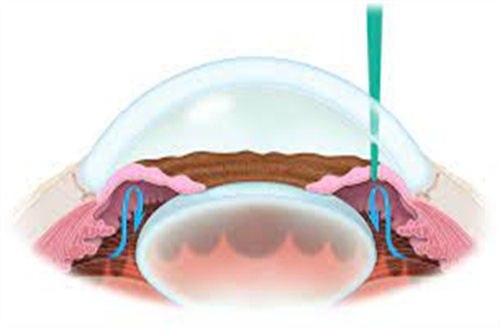

人工晶体依赖周边囊袋固定,若术中囊袋撕裂、术后剧烈运动或眼部受到外力撞击,晶体可能发生偏移或脱位。

患者会出现视力模糊、重影,甚至完全丧失视力。一位高度近视患者术后因搬运重物导致晶体脱位,需紧急手术重新固定晶体。

眼压波动:青光眼的“潜在推手”

手术可能影响房水循环,导致眼压升高。若眼压持续处于高位,会压迫视神经,引发青光眼。部分患者术后需长期使用降眼压药物,甚至接受激光治疗以控制病情。